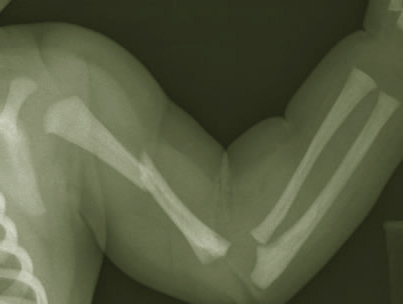

Перелом плечевой кости

Плечевая кость – это длинная кость верхней конечности, в которой анатомически выделяют тело (диафиз) и два конца (эпифизы). Около 7% всех переломов в травматологии занимает перелом плечевой кости и главной причиной являются удары и падения. Все эти травмы относятся к разновидностям перелома руки.

Какие бывают виды переломов плеча и плечевых костей

В зависимости от повреждения того или иного отдела плечевой кости, выделяют следующие виды переломов:

- Перелом в проксимальном отделе,который, в свою очередь, подразделяется на внутрисуставный (перелом головки и анатомической шейки плечевого сустава) и внесуставный (перелом бугорка плечевой кости и перелом хирургической шейки).

- Перелом диафиза плеча(различают перелом верхней, средней или нижней трети).

- Перелом в дистальном отделе.

Различают надмыщелковый и перелом мыщелков (чрезмыщелковый, Т- и У-образный межмыщелковый и изолированный перелом мыщелков)

В большинстве случаев наблюдается перелом верхнего конца плеча в районе хирургической шейки, а также прелом в области средней трети плеча и в месте расположения надмыщелков в нижней трети. В результате бытовой травмы чаще всего наступает закрытый перелом плечевой кости, не сопровождающийся повреждением кожи. Такие переломы лечатся проще всего и, зачастую, не вызывают осложнений.